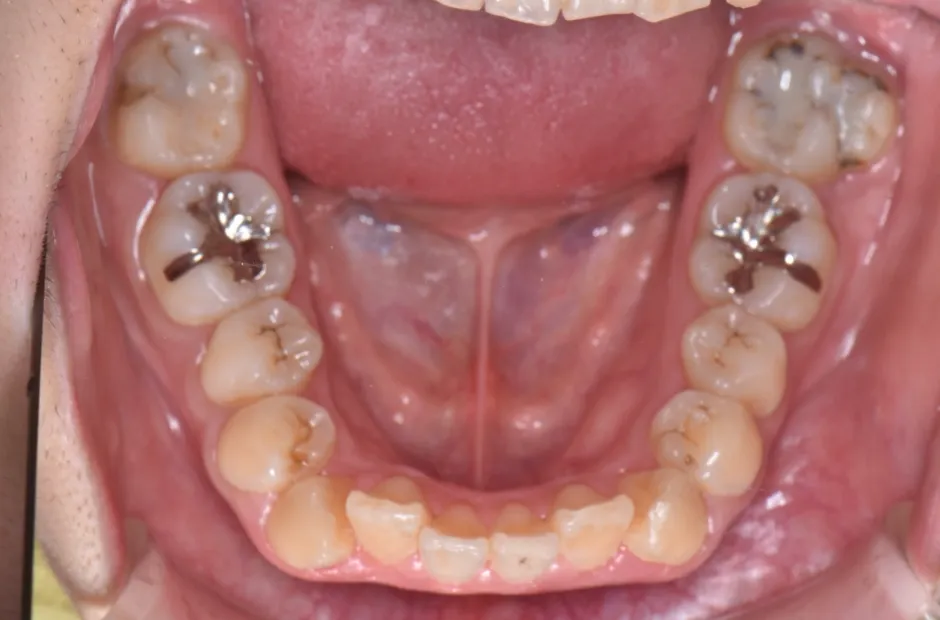

開咬

| 診断名・主訴 | 開咬 |

|---|---|

| 年齢・性別 | 18歳・男性 |

| 治療期間・回数 | 1年 12回 |

| 治療に用いた主な装置 | ロール付きリンガルアーチ |

| 抜歯部位 | なし |

| 治療費 | 70万円(税抜) |

| リスク・副作用 | 装置による違和感・疼痛・歯肉退縮・歯根吸収・虫歯のリスクなど |

治療前